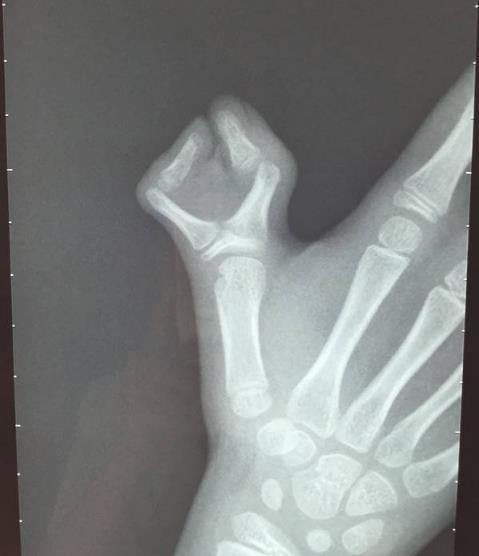

请问:患者目前肘关节还需手术吗?还是再次整复.